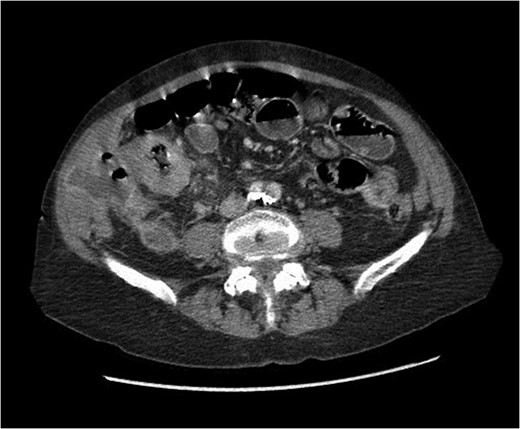

At presentation her vital signs were stable. Abdominal exam revealed exquisite tenderness in the right lower quadrant, with no evidence of digital clubbing. Blood-work revealed an elevated WBC of 15.6. A CT scan demonstrated a 4.3 cm annular mass within the cecum, suspicious for a primary colonic malignancy, as well as an 8.6 × 8.2 cm2 lobulated gas-containing abscess with extension in to the lateral abdominal wall (Figs 4 and 5).

Abdominal CT scan showing annular cecal mass with evidence of perforation.

Urgent exploratory laparotomy revealed a large cecal mass invading the abdominal wall with perforation and localized abscess formation. A right hemi-colectomy was performed with irrigation and washout of the abdomen. Source control was achieved and a primary anastomosis was performed with no diversion. A Jackson-Pratt drain was left in situ. She received 3 days of IV antibiotics with transition to oral antibiotics on POD 4. Her JP drain was removed on POD 3 and she was discharged on POD 5 without complication and with a prescription for oral antibiotics. After extensive histopathology review, the cecal mass was confirmed to be an invasive squamous cell carcinoma of lung origin (Fig. 6). Specimens were sent for immunohistochemical staining. Subsequent investigations included cystoscopy and urine cytology, which were negative for urogenital carcinoma.

Coronal view of abdominal CT scan showing cecal mass with evidence of perforation.